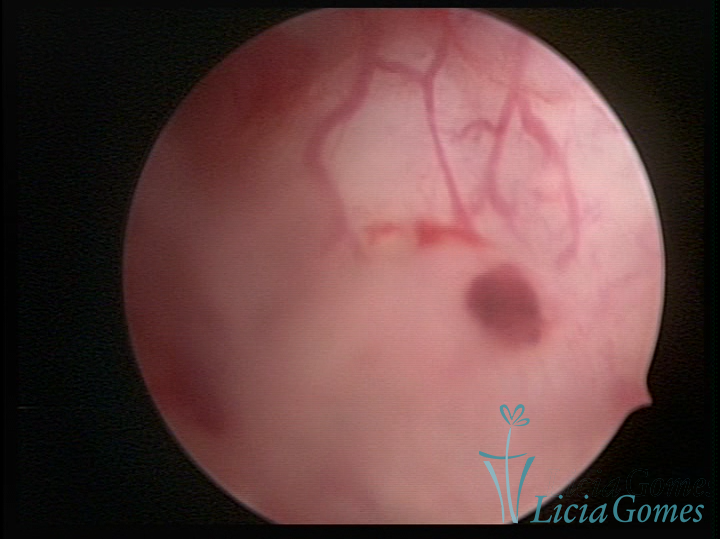

ADENOMYOSIS

The presence of endometrial tissue on the muscular layer of the uterus.

Video hysteroscopy allows diagnosing the lesions next to the superficial myometrial layers next to the endometrium, allowing the view of in situ, purplish, or chocolate brown lesions.